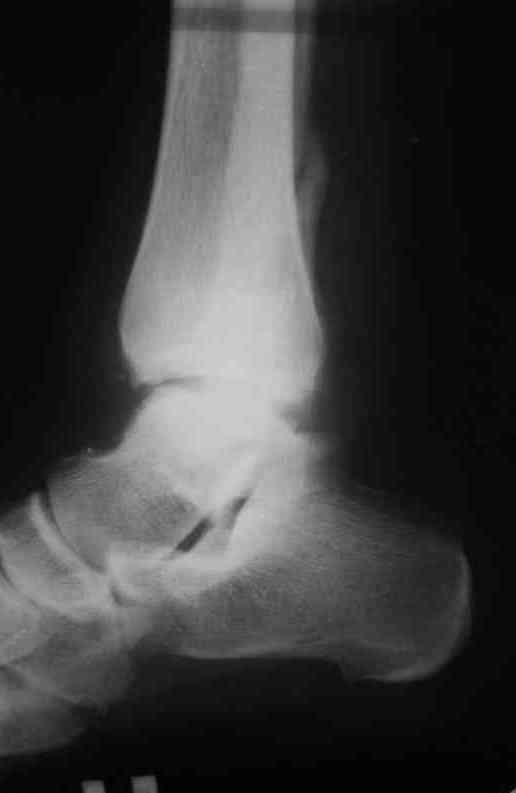

Уважаемые коллеги. Хотелось бы услышать ваше мнение по следующему случаю Обратился больной 23 года, травма 4 месяца назад - закрытый перелом наружной, внутренней лодыжки правой голени. Лечился консервативно, гипсовой иммобилизацией 8 недель, после снятия последней прошел курс восстановительного лечения. Беспокоят боли в области правого голеностопного сустава больше в проекции внутренней лодыжки, к вечеру. Отечность области сустава при физических нагрузках.Походка не изменена. Контуры правого голеностопного сустава сглажены. Имеется вальгусная установка правой пяточной кости. Объем движений в голеностопном суставе подошвенное / тыльное сгибание 50/0/80, безболезненные. Посоветуйте что делать в данной ситуации. Мне видится следующий вариант решения данной деформации: Восстановление нормальной анатомии голеностопного сустава - остеотомия малоберцовой кости и внутренней лодыжки, удалить все рубцы из области дистального межберцового синдесмоза, восстановить длину и устранить ротационное смещения наружной лодыжки.( встанет ли таранная кость на место?), фиксация наружной лодыжки пластиной, внутренней - винтами, дистального межберцового синдесмоза винтом. ЭОПом не располагаем. Что вы посоветуете? Где могут быть - технические трудности, <подводные камни>.

План вполне здравый. Но... Такое впечатление, что после устранения подвывиха суставные поверхности уже могут быть неконгруэнтны все равно.

То ли там есть импрессия в наружном отделе суставной площадки tibia, то ли не знаю что... IMHO не сильно криминальым выглядит и вариант

Доступ к наружной лодыжке лучше сделать передне внутренний что бы хорошо видеть неповрежденный внутренний угол суставной вилки - это будет референс для правильной позиции таранной кости.

Доступ к малоберцовой кости тоже нужен передне - наружный для того что бы была возможность выполнить остеотомию м.берцовой и остеотомию наружной части б.берцовой. Нет сомнений, что этот угол перенес компрессию. Если не опустить эту часть суставной поверхности , то невозможно будет компенсировать валгус. Для удержания фрагмента я бы использовал 3 кортикальный трансплантат из